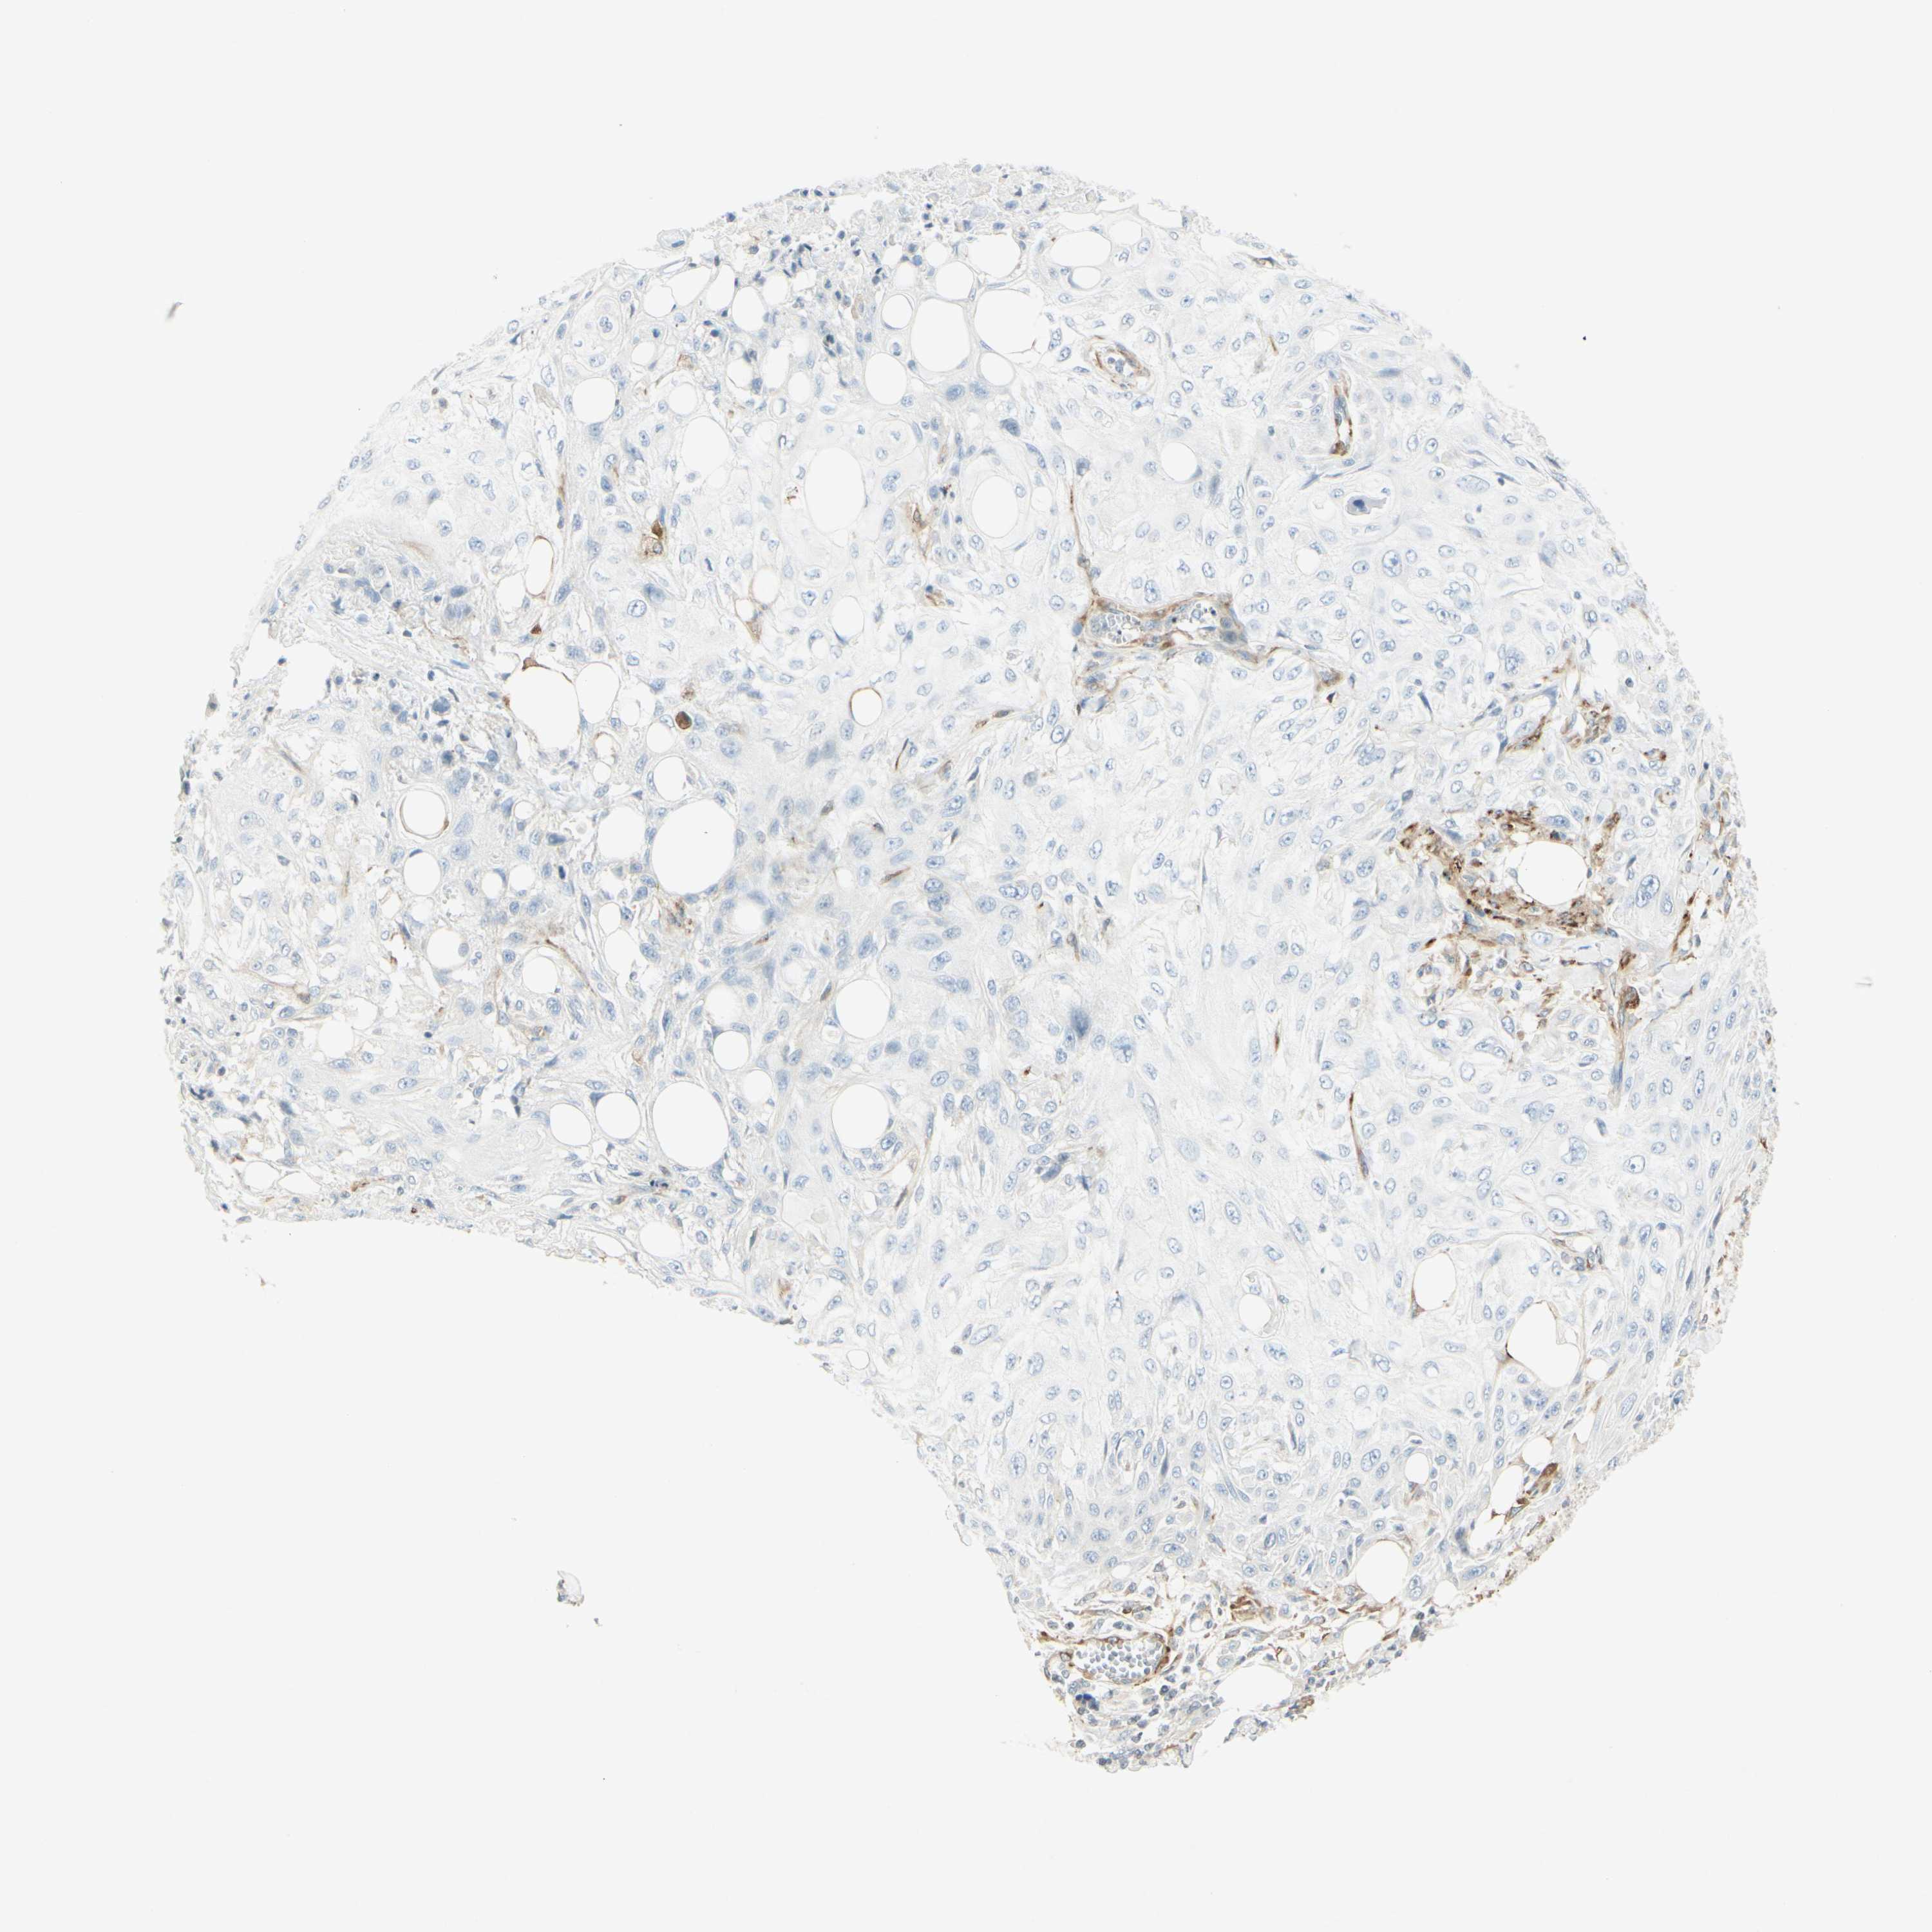

SKIN CANCER - Protein expressioni

A mouse-over function shows sample information and annotation data. Click on an image to view it in a full screen mode. Samples can be filtered based on level of antibody staining by selecting one or several of the following categories: high, medium, low and not detected. The assay and annotation is described here.

Antibody stainingi

Antibody staining in the annotated cell types in the current human tissue is reported as not detected, low, medium, or high, based on conventional immunohistochemistry profiling in selected tissues. This score is based on the combination of the staining intensity and fraction of stained cells.

Each image is clickable and will lead to virtual microscopy that enables deeper exploration of all samples and also displays staining intensity scores, fraction scores and subcellular localization as well as patient and tissue information for each sample.

Antibody HPA022275

Antibody CAB009792

Basal cell carcinoma

Squamous cell carcinoma, NOS

Squamous cell carcinoma, metastatic, NOS